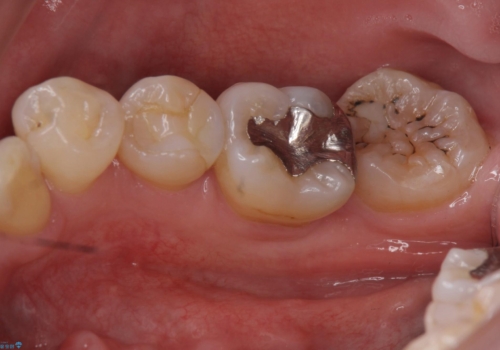

詰め物の下が虫歯 つぎはぎの歯をしっかり治療

詰め物の下が虫歯になっていました。

虫歯をしっかりとった後、セラミックで修復しました。

詰め物の下の虫歯は特に奥歯は大きかったのですが、神経を取らずに済みました。